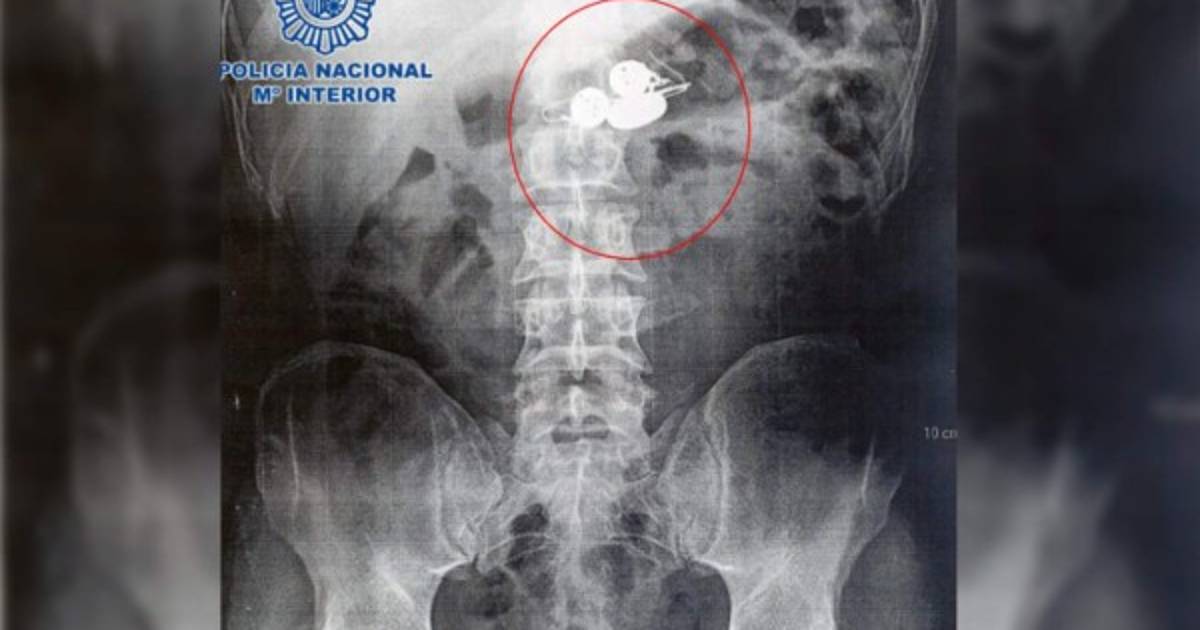

Los agentes se dieron cuenta de la acción y decidieron trasladarlo a un hospital para que los médicos les mostraron las radiografías de su organismo, en las que se advertía la presencia de varios objetos metálicos, con lo que se confirmaba que se las había tragado, según el Mundo.es

Esto obligó a que permaneciera durante tres días ingresado en el centro médico, hasta que las joyas fueron evacuadas.